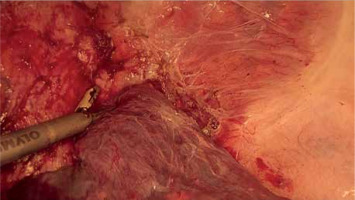

Ultrasonic devices (Photo 7), designed to dissect selectively liver parenchyma utilizing mechanical waves, preserving small vessels and bile ducts and sucking crushed liver parenchyma at the same time, maintain a dry operative field [41]. Therefore, ultrasonic devices are essential in major liver surgery.